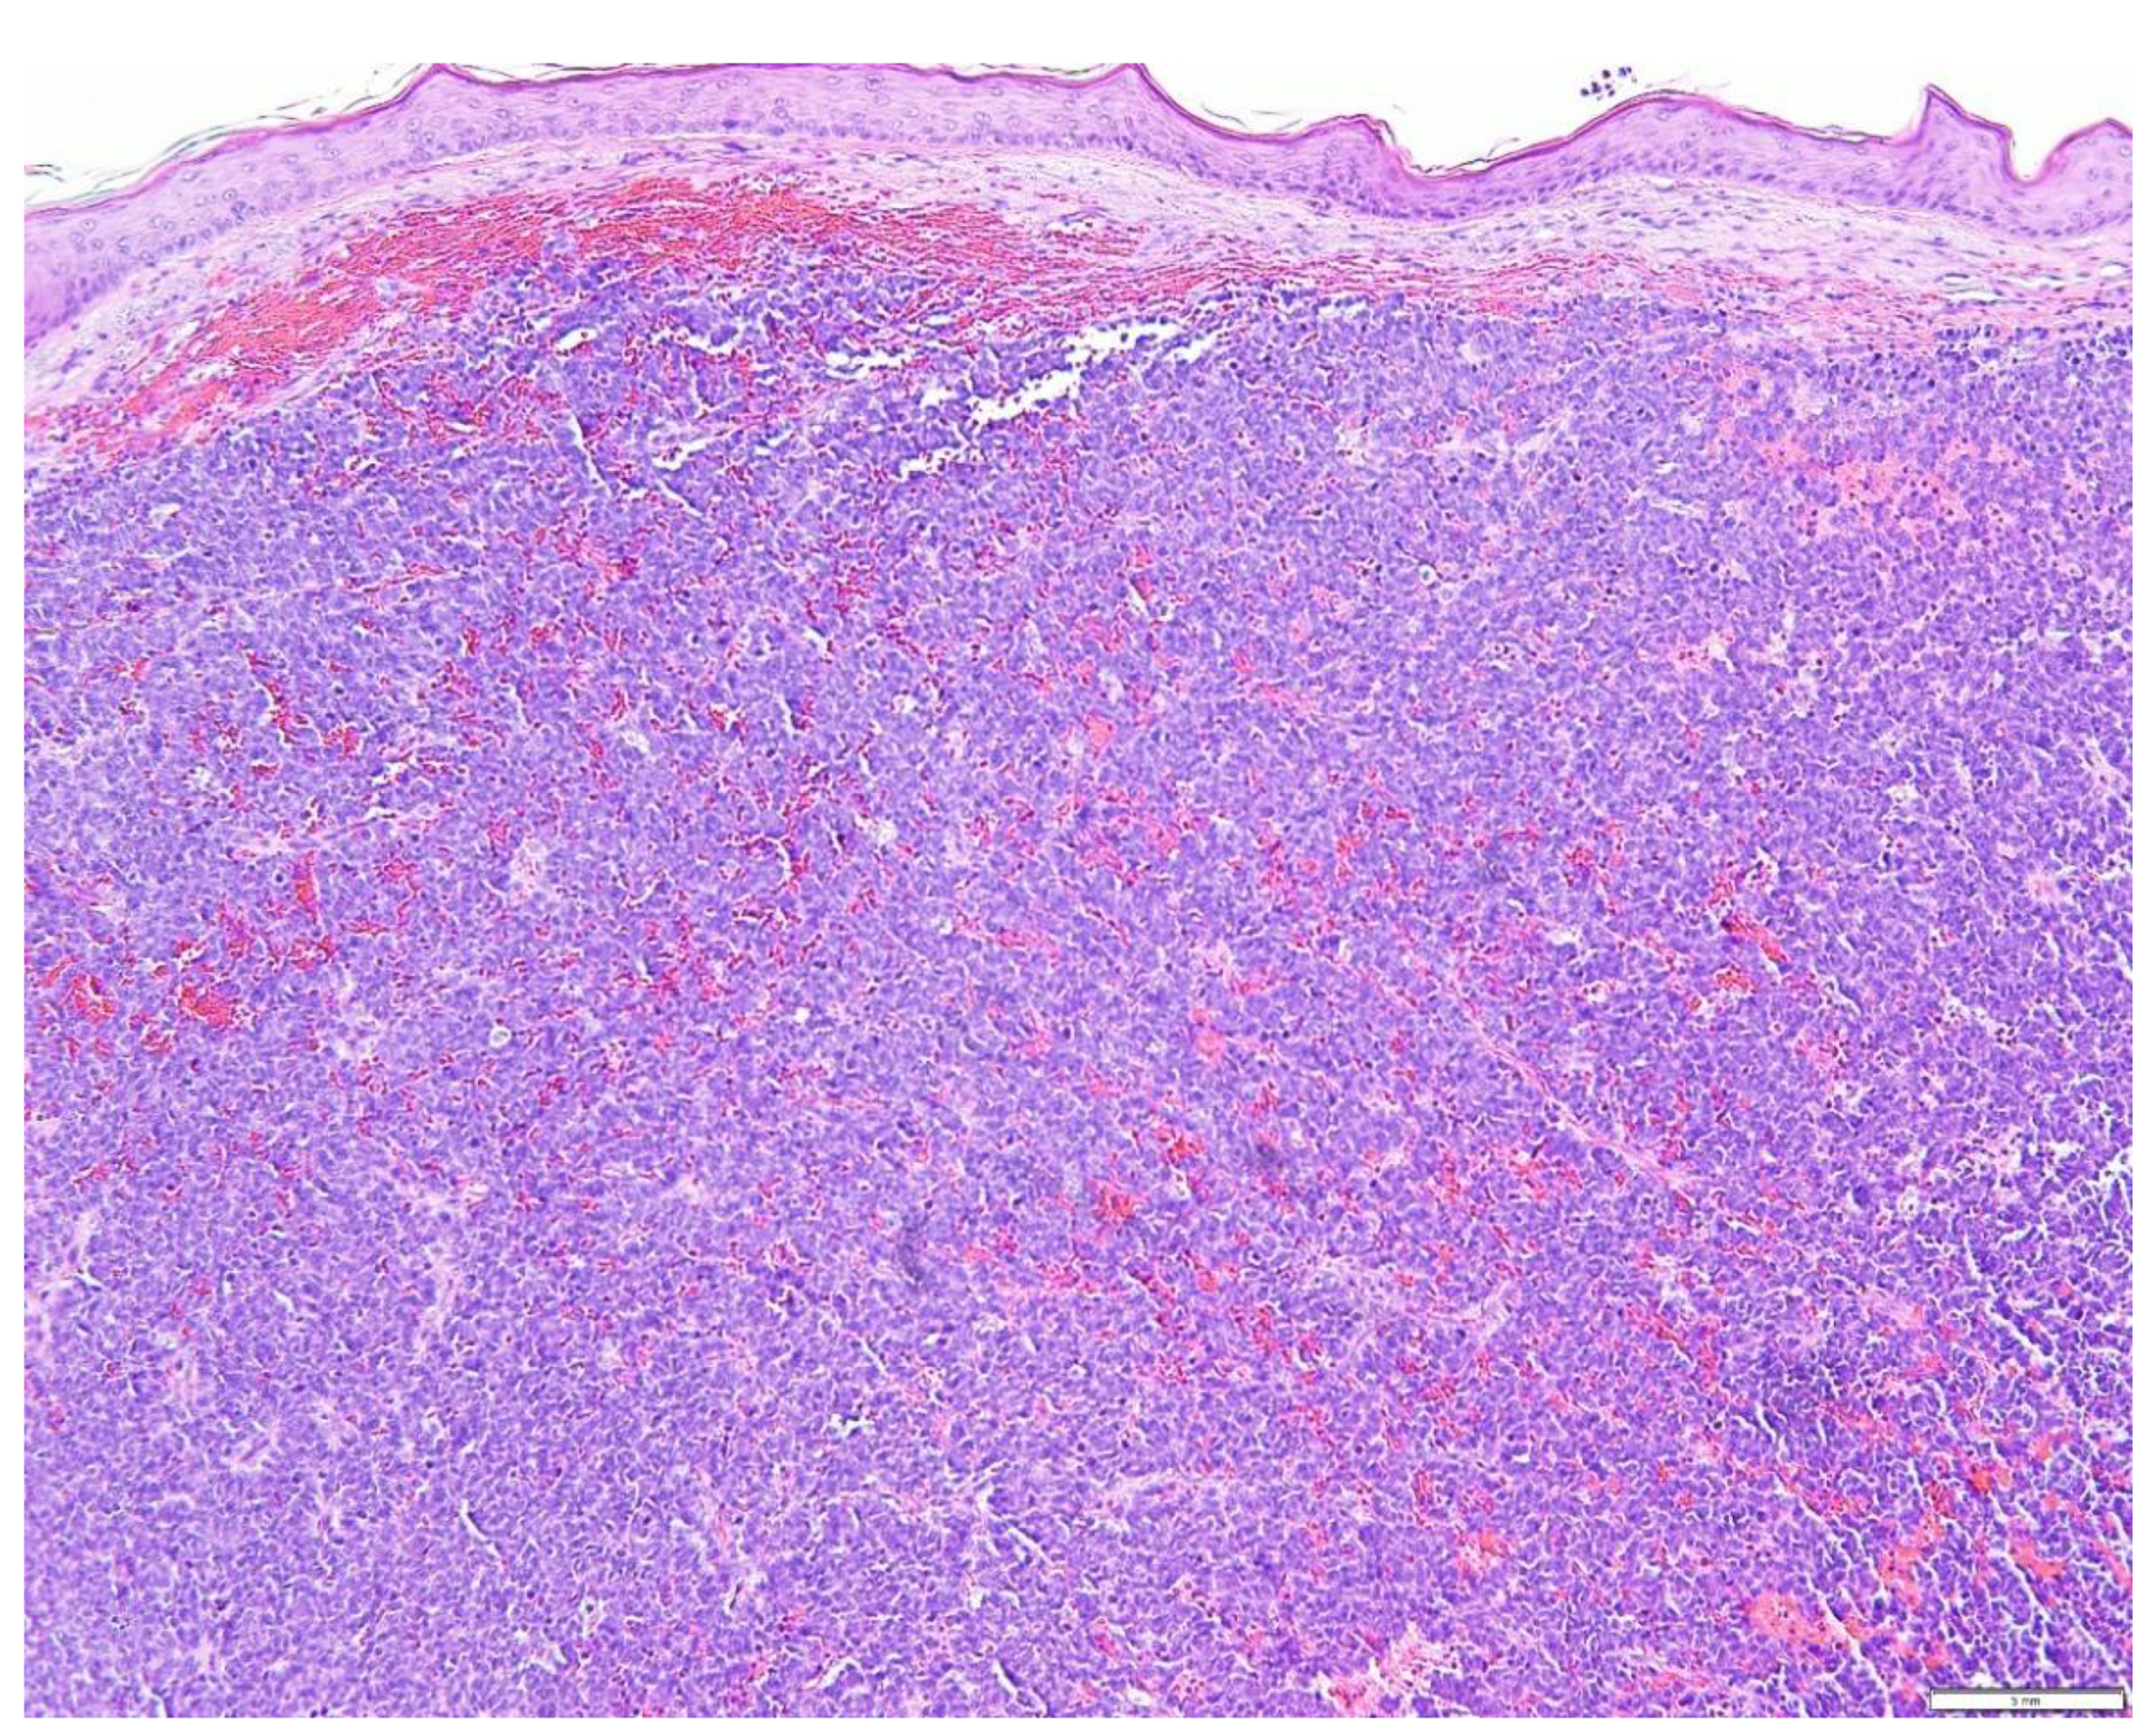

1. Introduction

5. Diagnostic Evaluation/Staging